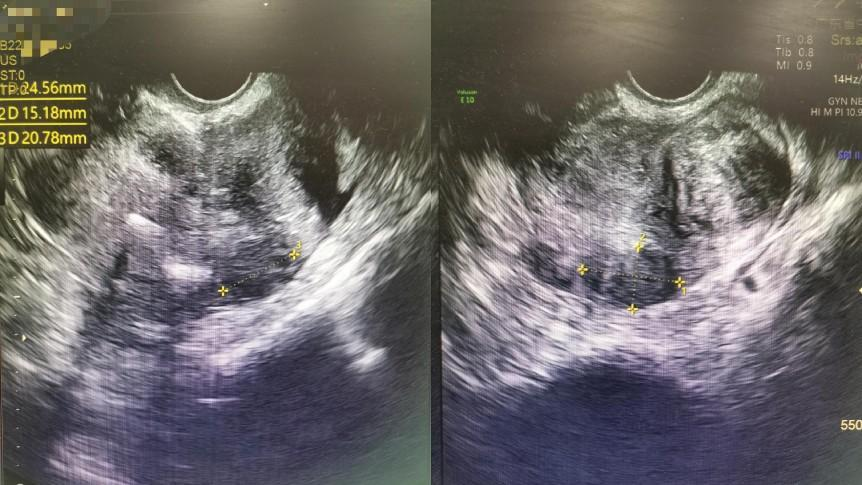

2021年欧女士已经到了绝经期,但她所期盼的子宫肌瘤变小的情况并没有发生,迎来的却是越来越大的腹围。原本欧女士还以为是长胖了所导致,但直到自己伴随出现明显的尿频以及大便难解症状时,她才紧张起来。2022年初,欧女士听闻广东省中医院二沙岛医院妇科黎小斌主任尤为擅长子宫肌瘤手术,便慕名前来就诊。经彩超检查后,欧女士体内数不清的子宫肌瘤着实让医生吓了一大跳。患者不仅子宫肌瘤特别多,而且血流信号丰富,数个较大肌瘤的直径均达5cm以上,子宫形态已经严重失常,随时有恶变可能。特别是当医生了解到患者已经出现了较为明显的二便改变现象,加上其自身体质也比较差,便建议患者及时考虑手术治疗。欧女士再三考虑后,终于下定决心要解决这个埋在身体的“不定时炸弹”。